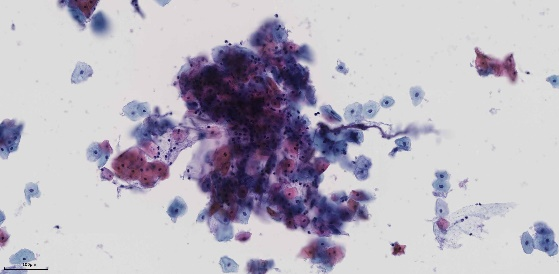

清晰捕捉细胞学样品的图像

SLIDEVIEW VS-M1

其他领军品牌